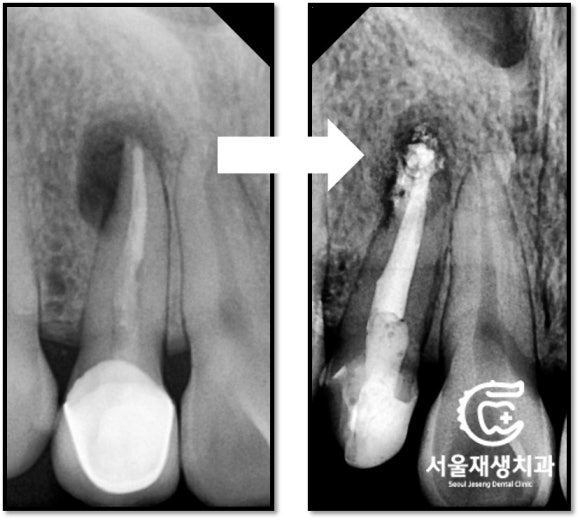

치료 전 후 엑스레이 사진입니다.

뿌리에 들어가는 기둥(포스트)를

다시 할 필요는 없다고 판단했습니다.

간단한 뿌리 충전과 (=신경치료)

간단한 머리 충전 (=레진충전) 및

크라운 치료로

모든 과정을 마무리했습니다.